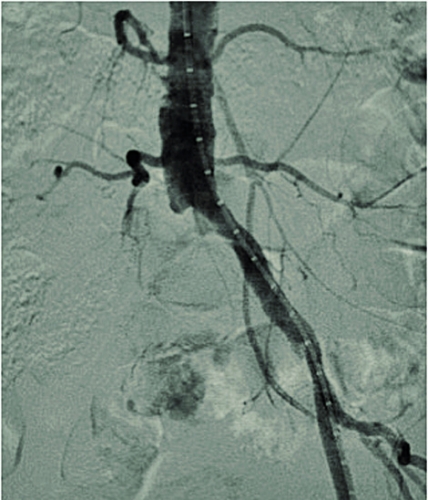

Kirurgisk/endovaskulär behanding

Invasiv behandling av benartärsjukdom innefattar dels öppen kirurgi (t ex bypass, trombendarterektomi), dels endovaskulär intervention (perkutan angioplastik, PTA, med eventuell stentning). Under 2009 utfördes i Sverige ca 3 500 infrainguinala ingrepp (öppna och endovaskulära); 60 procent av dessa på indikationen claudicatio. Det finns endast begränsad evidens för effekt av invasiv behandling vid claudicatio (till skillnad från vid kritisk ischemi).

Endovaskulär behandling av claudicatio har undersökts i flera studier. En multicenterstudie [33] visade att PTA vid både supra- och infrainguinal sjukdom hade en adjuvant effekt på den absoluta gångsträckan hos patienter som redan erhållit riskfaktormodifiering och gångträning. Ytterligare en studie [25] visade på snabbare klinisk förbättring efter PTA jämfört med strukturerad gångträning. Effekten var dock inte lika stor i båda grupperna efter ett år.

Endovaskulär behandling (PTA med eller utan stent) av suprainguinala lesioner ger en utmärkt öppetståendefrekvens (patency) på både kortare och längre sikt och bör vara förstahandsalternativ när anatomiska förutsättningar finns. Andra alternativ är aortobifemoral bypass och axillobifemoral bypass. Det förstnämnda ger en mycket god öppetståendefrekvens men är ett stort kirurgisk ingrepp med större risk för peroperativa komplikationer. Det senare utförs sällan på indikationen claudicatio på grund av sämre öppetståendefrekvens och ökad risk för bl a graftinfektion.

Vid infrainguinal sjukdom är öppetståendefrekvens- och komplikationsprofilen för både öppna och endovaskulära åtgärder inte lika gynnsamma som vid suprainguinal sjukdom. Vid claudicatio är tröskeln för behandling något högre. PTA ger vid korta, enstaka eller multipla lesioner i a femoralis superficialis (SFA) god öppetståendefrekvens och är enligt de senaste TASC-riktlinjerna [10] förstahandsalternativ. Vid långsträckta kroniska SFA-ocklusioner, där återfyllnad sker i antingen poplitea ovan eller nedom knäleden, kan femoropopliteal bypass vara ett alternativ om tillgång till egen ven finns då syntetgraft ger betydligt sämre öppetståendefrekvens. Mer långsträckta lesioner och lesioner som involverar trifurkationen ger sämre behandlingsresultat både öppet och endovaskulärt, och behandling i dessa kärlsegment förbehålls oftast patienter med kritisk ischemi.